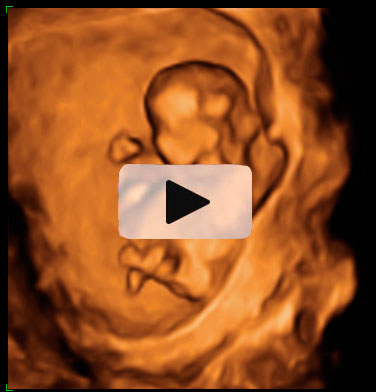

Ecografía 3D de la semana 9: Trillizos

Cada uno de los bebés crece en su bolsa amniótica

En esta ecografía en tres dimensiones (3D) se ve un embarazo de trillizos de 9 semanas. Uno de los bebés, "crece" solo dentro con una bolsa y placenta independiente. Más abajo se aprecian a otros dos bebés que también se desarrollan en bolsas independientes.

Ecografía de trillizos de 9 semanas en 3D

En la imagen se ve un embarazo de trillizos de 9 semanas tomado por un ecógrafo en tres dimensiones (3D). Se diferencia perfectamente en la parte superior de un primer bebé "en solitario" con su bolsa y placenta independientes. Una membrana gruesa le separa de sus hermanos, que se gestan con él en el útero materno. Precisamente en la parte inferior de la imagen podemos observar a los dos gemelos en bolsas también independientes, con una fina membrana de separación entre ellos.